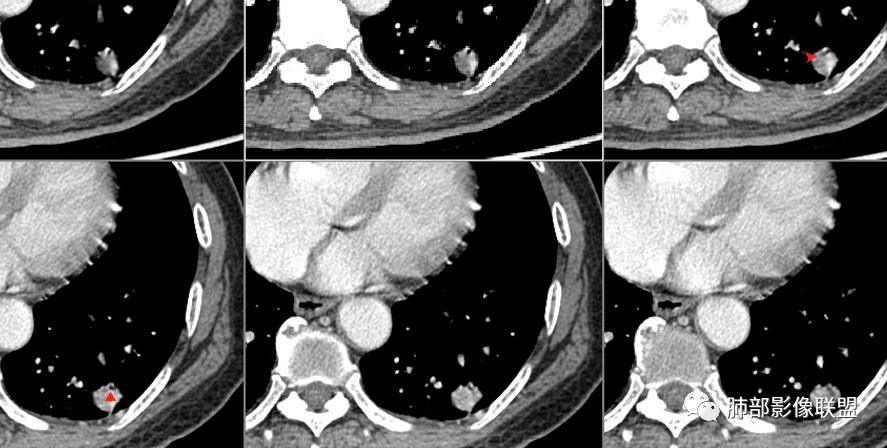

病例1病理结果

病例2病理结果

病例小结

应当说两例患者影像学表现都具有比较明显恶性征象,中老年男性患者,均都没有呼吸系统临床症状。

病例1为胸膜下实性小结节,血管脐凹样出入,可见支气管阻塞。病灶膨隆,部分边缘平直,周围晕征不明显,未见分叶,但可见毛刺及胸膜牵拉,增强后明显强化,老年男性,怀疑新生物尤其是腺癌是有理由的。

病例2肉瘤样癌的病理意见有些出乎预料,也充分说明病变及影像表现的复杂性。病灶小结节支气管截断、空泡、分叶、短毛刺、血管集束征等似乎均符合肺癌的影像特性。肺鳞癌及肉瘤样癌往往范围较小就可以出现坏死,但如果结节太小则很少能够在影像上观察到坏死区或空洞,没有增强扫描图像更是如此。